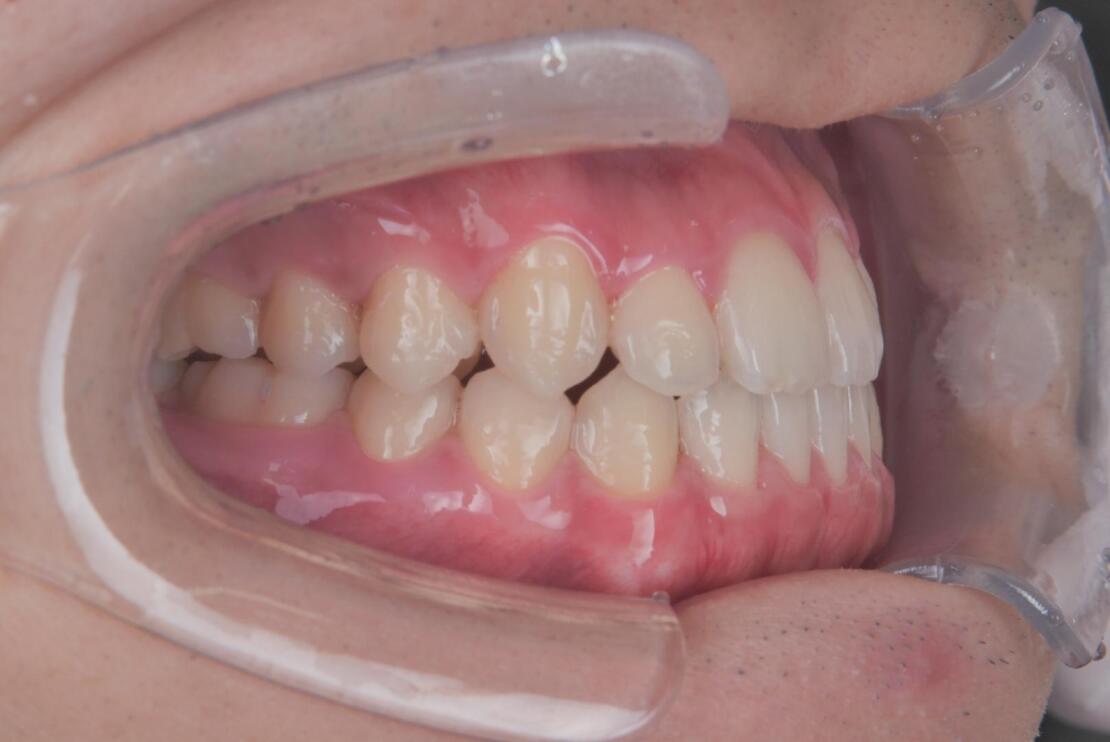

After 1

After 2